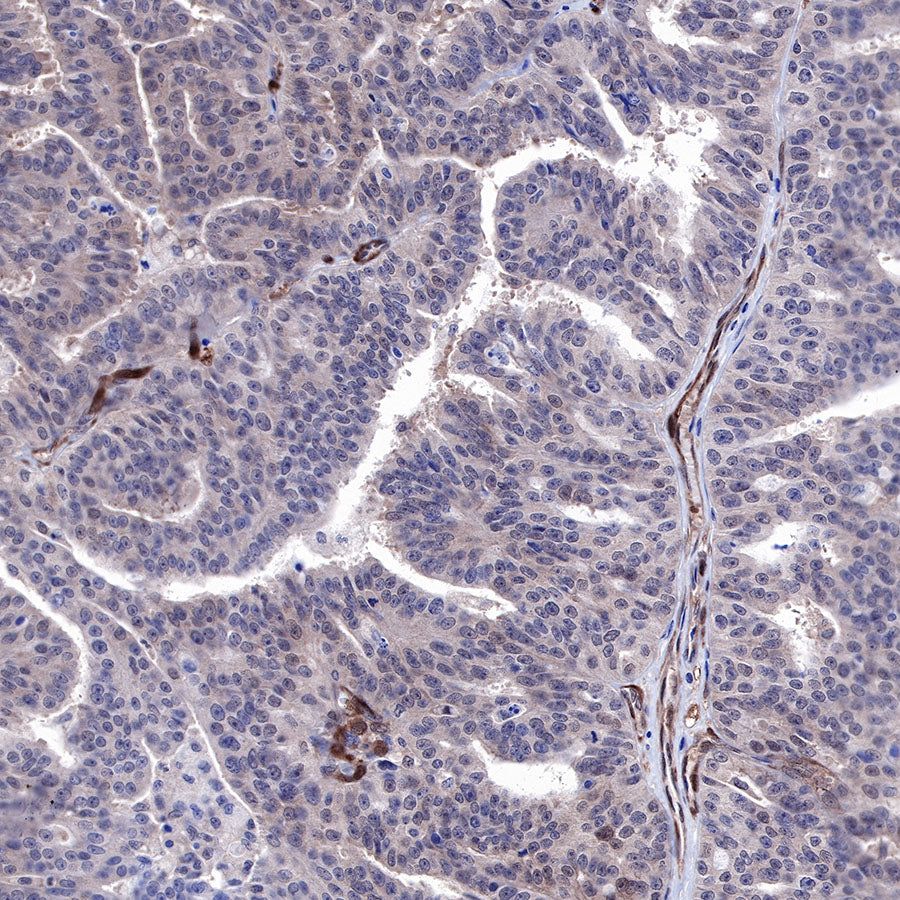

Immunohistochemistry

IHC shows positive staining in paraffin-embedded human ovarian carcinoma. Anti-PTEN antibody was used at 1/500 dilution, followed by a HRP Polymer for Mouse & Rabbit IgG (ready to use). Counterstained with hematoxylin. Heat mediated antigen retrieval with Tris/EDTA buffer pH9.0 was performed before commencing with IHC staining protocol.